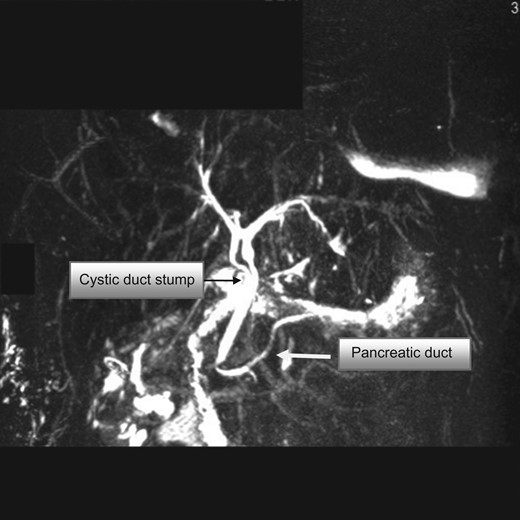

MRCP showing the double common bile duct, cystic duct stump and pancreatic duct. The cystic duct stump is noted to open distally into the common duct.